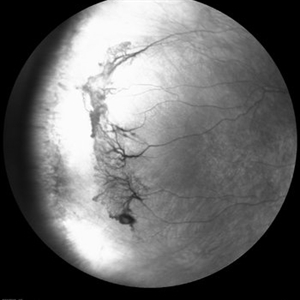

Sickle cell retinopathy (Proliferative) (2 files)

Sickle cell retinopathy (Proliferative) (2 files)

Proliferative sickle retinopathy (1 file)

Proliferative sickle retinopathy (1 file)

Proliferative Sickle Cell Retinopathy (Stage3) (10 files)

Proliferative Sickle Cell Retinopathy (Stage3) (10 files)

Sickle Cell Retinopathy (11 files)

Sickle Cell Retinopathy (11 files)

Sickle Cell Retinopathy SC (6 files)

Sickle Cell Retinopathy SC (6 files)

Sickle Cell (1 file)